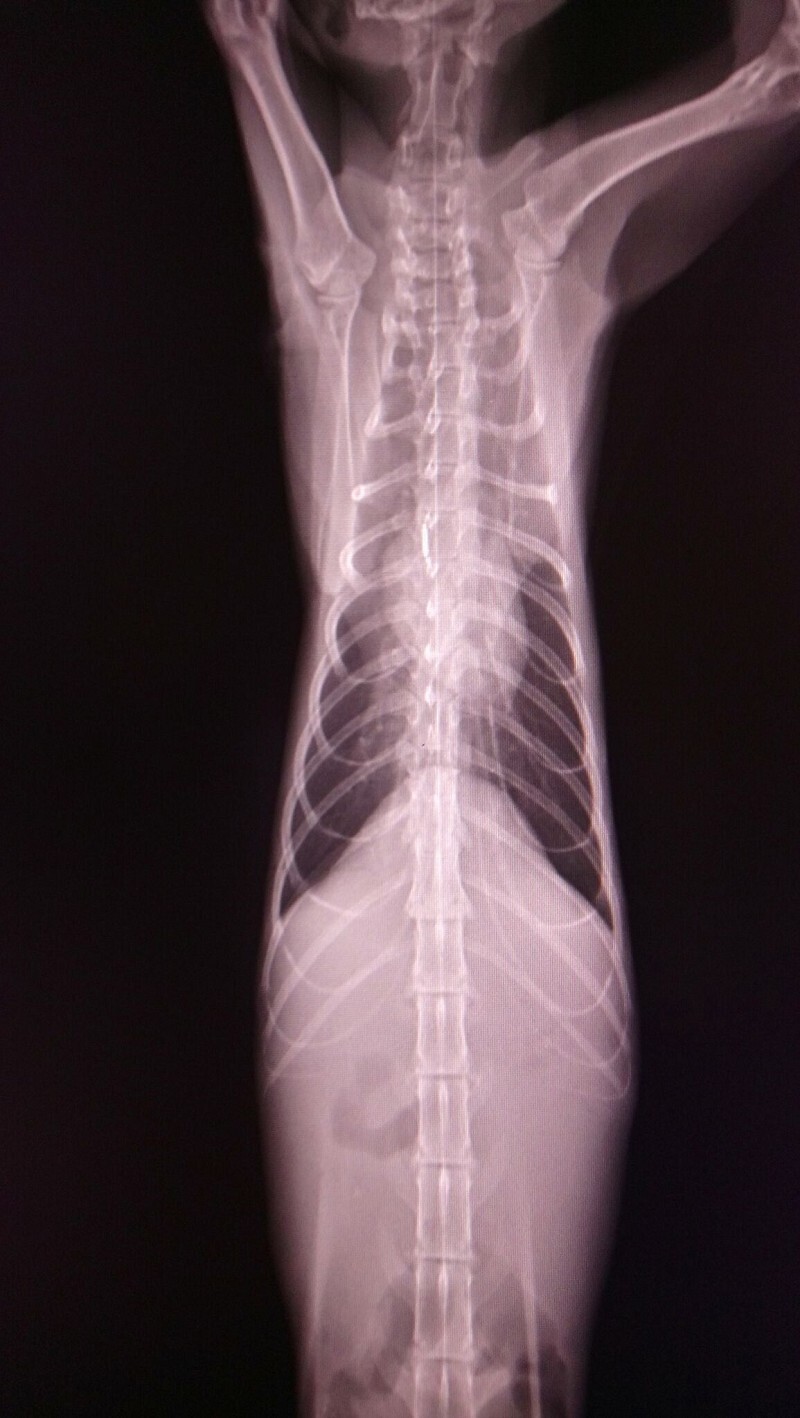

經醫師檢查發現瘦瘦有中度貧血.白血球極度偏高.黃疸.肝指數輕微偏高

也是愛滋感染的貓咪

超音波檢查發現腎腫大且大部分病灶都在腎臟皮質處.有少量腹水動物近況說明: 住院治療前醫師就有說貓咪狀況不樂觀